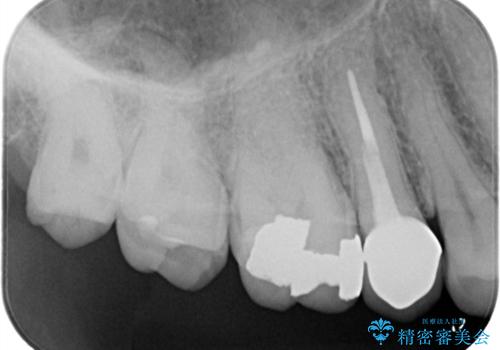

- 長年使用してきた奥歯の古い銀歯のやりかえを主訴にご来院されました。診査の結果、銀歯の下の歯質が薄くなっている部分があり、今後強い力が加わると歯が割れてしまう(破折)リスクが高いと判明しました。このリスクを回避し、歯を長期的に守るため、歯全体をしっかり覆う**セラミッククラウン(被せ物)**による修復を提案。機能的な強度と自然な見た目の両立を目指しました。

治療では、まず古い銀歯を慎重に取り外し、内部の虫歯の有無を確認しました。その後、残っている歯質を保護し、強度を高めるために、適合性に優れたオールセラミッククラウンを作製・装着しました。

強度: 歯全体を覆うため、咬合力による歯への負担を分散させ、破折リスクを大幅に軽減します。